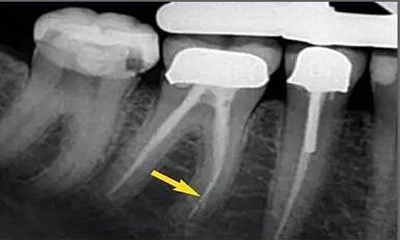

從近遠(yuǎn)中向的X光片可以看出,在根尖三分之一區(qū)域,根管形態(tài)較寬而且彎曲。通過彎曲之后,單只銼沿直線到達(dá)根尖,沒有清理的根管的唇側(cè)部分。遺漏的區(qū)域在近遠(yuǎn)中向的X光片中顯示得格外清晰。

唇面觀

近遠(yuǎn)中觀

預(yù)備后的根管橫切面